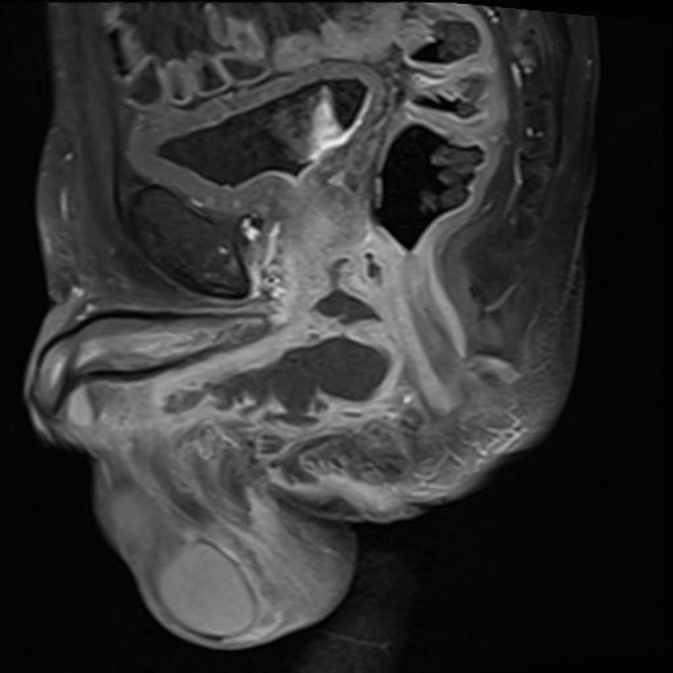

The patient was discharged on Day 7 with instructions for endocrinology follow-up to manage his diabetes. Follow-up MRI at 4 weeks showed a regression of the previously described collection with almost complete resolution of the abscess in the corpus spongiosum and proximal urethra. As seen in Figure 4 and Figure 5, Urethral evaluation at 3 months (via history taking about urine flow) showed a good stream.

Figure 4. Follow-up Coronal T2-weighted MRI obtained 4 weeks after surgical drainage demonstrating near-complete resolution of the previously identified periurethral abscess.

Figure 5. Post operative axial T2-weighted MRI showing interval resolution of soft tissue enhancement and absence of residual periurethral collection.